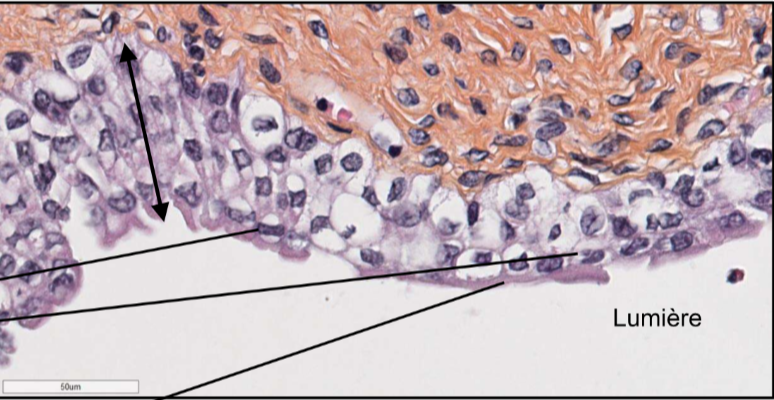

Decrit lepithelium sur cette lame et d’où elle provient

Epithelium pseudostratifié (une seule couche de cellule mais les noyaux sont a une hauteur differente) cylindrique cillié

La trachée!